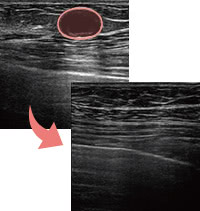

除去したアクアフィリング

完全に溶解しないケースでも、エコー下できれいに吸引除去

生理食塩水でも溶けにくい

生理食塩水で簡単に溶解できるとされるアクアフィリング豊胸やアクアリフト豊胸ですが、実際に行うとヒアルロン酸よりも溶けにくいと感じるケースもありました。